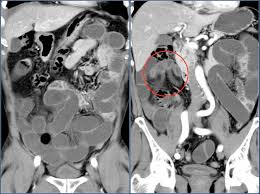

They show the different appearances of acc lung mets. Other names for this test: What is a ct scan with contrast? If not spread, you could conceivably see obstruction or changes in the bowel wall but it would likely be a big tumor nonetheless. I was then directed to lay down on the table.

Abdominal And Pelvic Ct from www.radiologyinfo.org The computer puts them together to make a 3 dimensional (3d) image. Early colorectal cancer can be subtle on ct scans showing only mild wall thickening, small polyps, or subtle lymph nodes in atypical draining location. Nothing found on us scan but fatty liver. I had my half way scan today so i'm now on. This shows the cancer more clearly. Acc has a tendency to spread to the lungs among other organs. Lab tests used to diagnose kidney cancer include: They show the different appearances of acc lung mets.